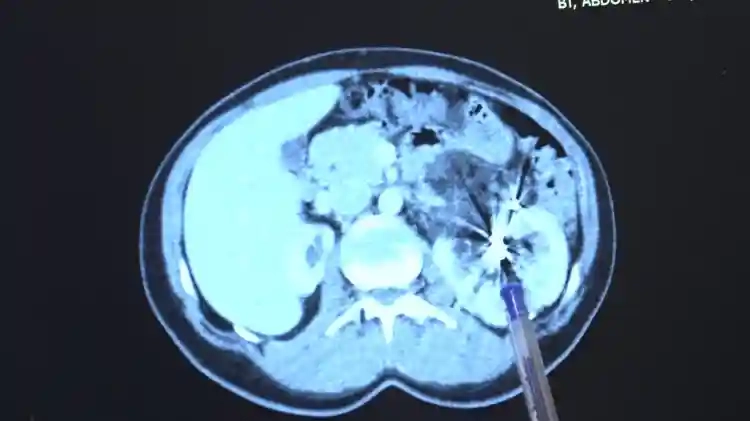

Tek böbrekli hastayı diyalizden kurtarıp sağlığına kavuşturdu. Zorlu bir ameliyatı başarıyla tamamlayan Bursa Medicana Hastanesi Üroloji Uzmanı Doç. Dr. Ahmet Şahan, hastanın durumunun şuan iyi olduğunu belirterek, “Nurcan Hanım 35 yaşında bize İzmir'den geldi. Doğuştan tek böbrekli bir böbreği küçük olduğu için işlevsiz durumda. Sağlam böbreğinde ise 2016'da tanısı konmuş giderek büyüyen iyi huylu "anjiomyolipomu" denilen 12 santimetre boyutunda bir kitlesi var. Bu kitle artık böbreğin damarlarını içerisine almış komplike bir kitle durumunda. Hastaya iki kez anjioembolizasyon tedavisi uygulanmış fakat başarısız olduğu için kitle büyümeye devam etmiş. Kadınlarda 4 santimetreden büyük anjiomyolipomular kendiliğinden kanayarak yaşamı tehlike altına attığı için bu kitlelerin alınması gerekiyor. Tek böbrekli olunan durumlarda böbreğin tamamen alınması durumu da söz konusu olabiliyor. Bu riske girmemek için çoğu merkez de embolizasyona başvurmuş. Hasta bize geldiğinde bu işi yapabileceğimizi söyledik. 2 saat süren kapalı bir ameliyatla kitleyi tamamen çıkardık ve hastamızı 3 gün içerisinde taburcu ettik. Hastamızın değerli şuan iyi durumda. Hastamızı diyalizden kurtarıp kapalı bir ameliyatla sağlığına kavuşturabildiğimiz için çok mutluyuz” dedi.